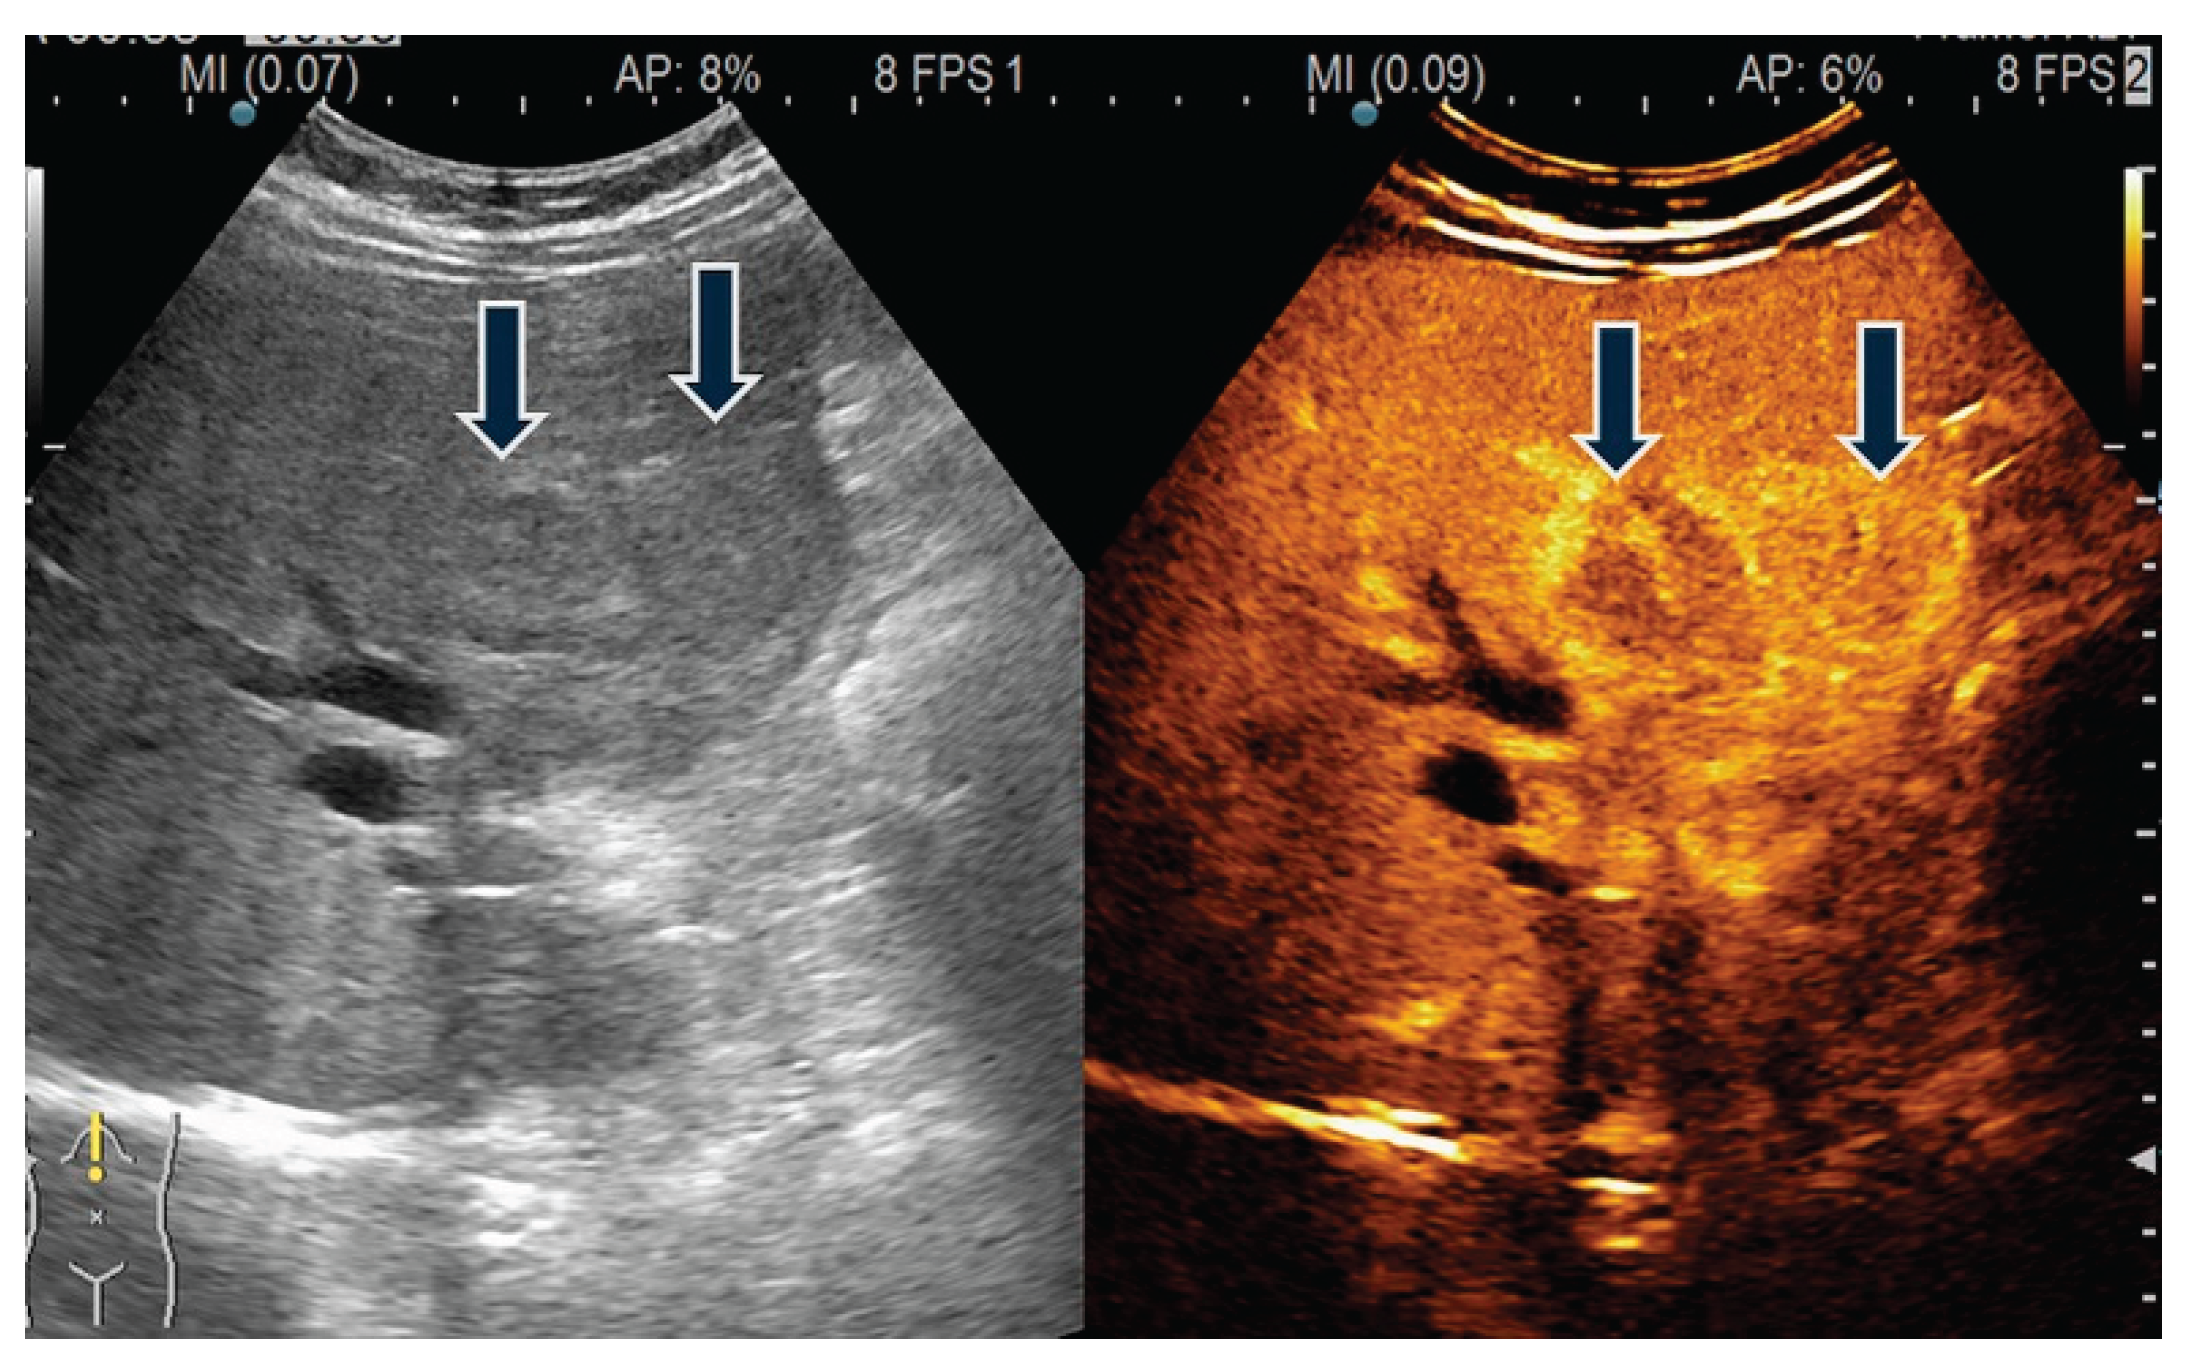

- Zhu, L.; Li, N.; Zhu, Y.; Han, P.; Jiang, B.; Li, M.; Luo, Y.; Clevert, D.A.; Fei, X. Value of high frame rate contrast enhanced ultrasound in gallbladder wall thickening in non-acute setting. Cancer Imaging. 2024, 24, 7. [Google Scholar] [CrossRef]